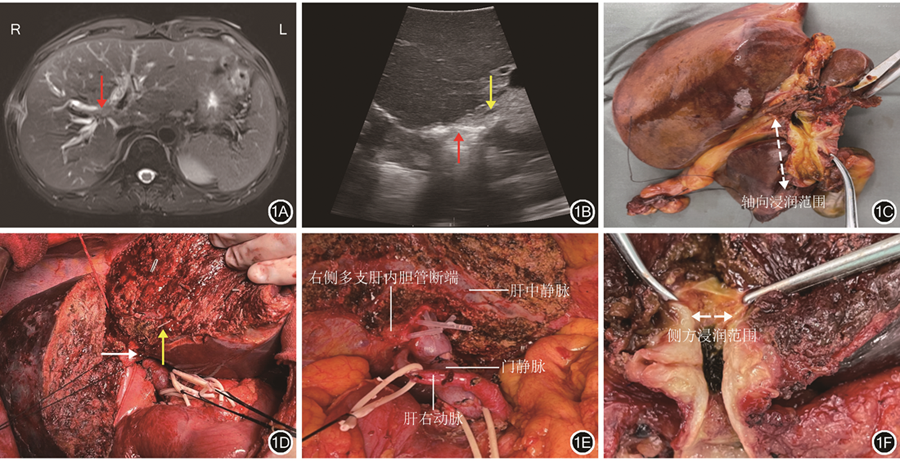

由于劈开肝脏后肝门部胆管已完全显露,气体干扰和难于耦合使得术中探头,无论是经过肝脏还是直接放置于胆管表面,都不能清晰显示胆管壁各层结构,因此,开腹术中超声检查只能进行粗略导航。示例1:患者男,63岁,发现皮肤、巩膜黄染2周入院,术前MRI检查结果提示肝门部胆管占位并肝右叶占位。有糖尿病史。行肝动脉受累肝门部胆管癌扩大根治术,术中切除右半肝及肝外胆道,行门静脉及肝动脉重建。63岁男性患者术前影像学检查结果及开腹术中超声检查结果见图1。